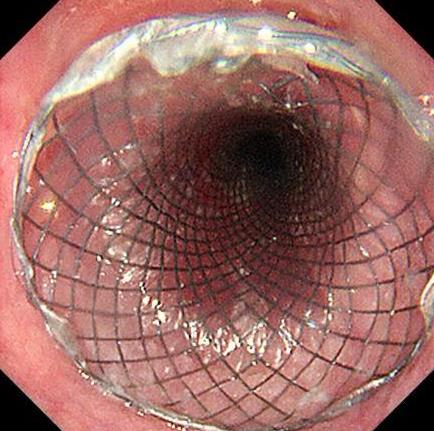

• 内镜测距盲推置入覆膜食管支架治疗晚期食管癌的临床疗效(附182例报告)

2025, 31(7):86-90. DOI: 10.12235/E20240691

摘要 (144) HTML (103) PDF 985.31 K (118) 评论 (0) 收藏

摘要:目的 探讨内镜测距盲推置入覆膜食管支架治疗晚期食管癌的临床疗效。方法 回顾分析2014年1月-2023年12月该院采用内镜测距盲推置入覆膜食管支架治疗的182例晚期食管癌患者的临床资料。观察操作时间、患者舒适度、支架置入位置是否准确、术后出血和胸痛等情况。结果 182例均成功置入支架,平均置入时间(11.0±4.0)min,支架位置较预期位置相差的距离≤0.5 cm,术后6 h进食半流质,置入过程中,未出现明显恶心、呕吐和呛咳等症状,术后出血25例,发生率为13.7%,不需要静脉麻醉,术后未发生穿孔,术后胸痛发生率为82.4%,患者吞咽困难得到明显缓解。结论 内镜测距盲推置入覆膜食管支架用于晚期食管癌伴食管梗阻患者,具有操作简便、支架位置准确、并发症少和患者不适感轻等优点,可作为临床食管支架置入的一种新选择。